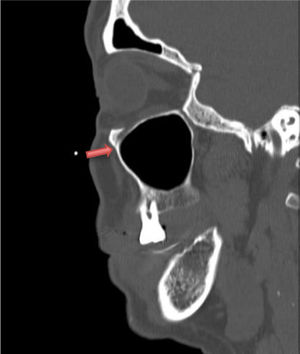

En Urgencias se solicita recuento de LCR y TC craneal en la que se identifica desmineralización a nivel de fóvea etmoidal izquierda de 2mm (fig. 1) sugestiva de solución de continuidad a nivel de fosa craneal anterior. Finalmente, la paciente ingresó a cargo del Servicio de Neurocirugía ante la confirmación de la presencia de fístula de líquido cefalorraquídeo traumática que precisó intervención quirúrgica para su reparación.